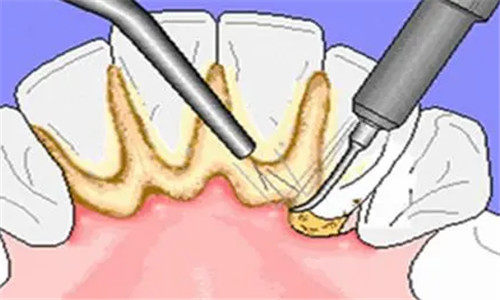

三、基础治疗项目价格

基础治疗项目是维持口腔健康的重要环节,安塞区人民医院口腔科在这些项目上也有着合理的收费。

超声波洗牙:300 元起

牙周病筛查:80 元起

牙周病治疗:200 元起